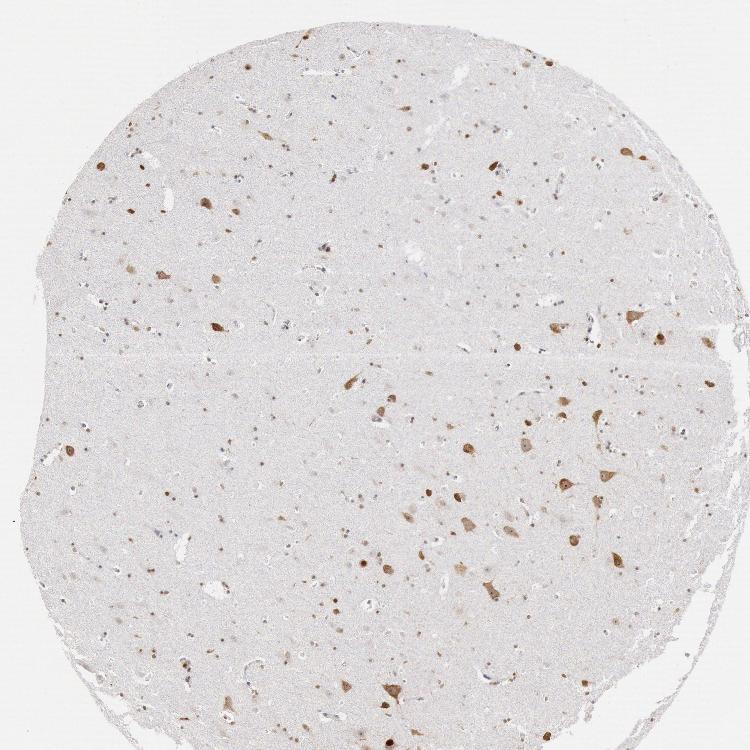

HIPPOCAMPUS - Antibody stainingi

Antibody staining in the annotated cell types in the current human tissue is reported as not detected, low, medium, or high, based on conventional immunohistochemistry profiling in selected tissues. This score is based on the combination of the staining intensity and fraction of stained cells.

Each image is clickable and will lead to virtual microscopy that enables deeper exploration of all samples and also displays staining intensity scores, fraction scores and subcellular localization as well as patient and tissue information for each sample.

Antibody HPA001311Antibody CAB015351

Glial cells MediumLow

Neuronal cells MediumHigh